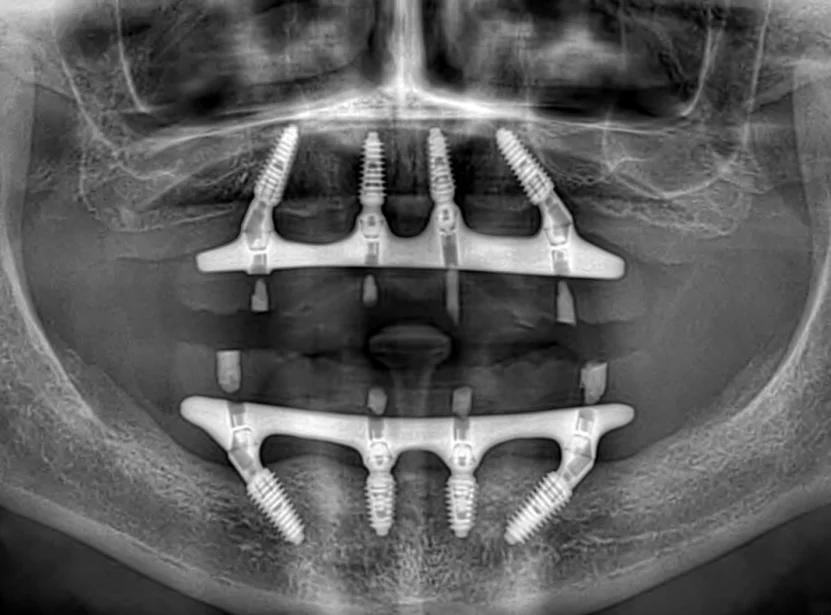

Долгое время откладывал лечение, потому что боялся сложной операции и долгого восстановления. Жил с постоянным дискомфортом и ограничениями в питании, но не решался сделать первый шаг. Длительное отсутствие зубов на верхней и нижней челюсти привело к потере жевательной эффективности и опоры мягких тканей.

На консультации мы подробно разобрали все этапы лечения, ответили на все вопросы и подобрали комфортный и безопасный план. По протоколу All-on-4 на обеих челюстях установлены несъёмные конструкции.

Уже в день операции пациент получил новую улыбку. Обеспечена стабильность прикуса, полноценная функция и выраженное улучшение лицевых пропорций за счёт восстановления опоры тканей.